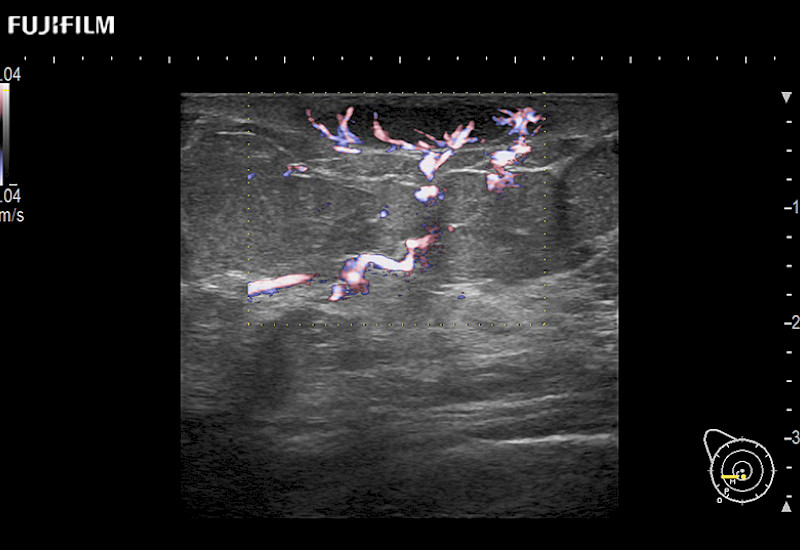

The ARIETTA 750 incorporates all of the proven technologies and functions that medical professionals have come to expect from Fujifilm Healthcare.

ARIETTA 750 is the definitive diagnostic ultrasound solution for any clinical setting - Private Office, Imaging Center, or Hospital. The ARIETTA platform provides the ultimate in clinical performance with its state-of-the-art features and large user-friendly display.

The ARIETTA 650 DI combines trusted Fujifilm Healthcare technologies and features tailored for surgical oncology.

Designed to meet the demands of surgeons, the ARIETTA 650 DI offers precise guidance. Its advanced capabilities and large, intuitive display offer accurate and efficient care in operating rooms and specialized surgical settings.